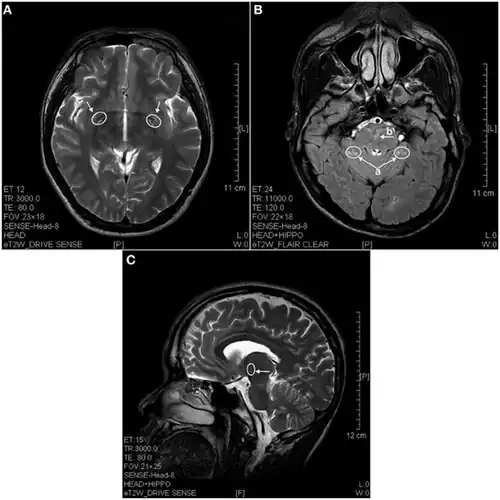

In 2013 a study using magnetic resonance imaging showed brain lesions in ketamine addicts (using from 0.2g twice a week up to 1g daily for 0.5 up to 12 years) with severity depending on the duration of addiction and daily intake of ketamine. Cortical atrophy and holes in superficial white matter are seen early on. After 4 years of addiction lesions spread throughout the brain and damage is evident in the pons and other deeper brain structures.[17]